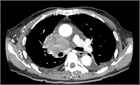

病態

1. 上大動脈症候群とは、上大静脈の閉塞や狭窄によって生じる上半身からの静脈血の還流障害により、静脈圧の上昇を来し、頭部、顔面、上肢、頚部および上半身のうっ血・浮腫を来す症候群である。

1. その原因として肺癌など胸部悪性疾患が多く、腫瘍に関連する救急疾患(Oncologic emergency)の1つに位置づけられている。